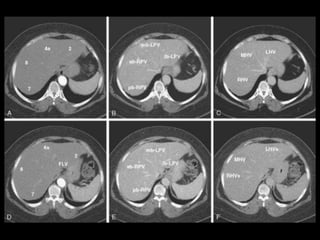

Subdivisão Funcional

• Os oito segmentos são divididos:

– A primeira divisão é realizada dividindo através da

Porta Hepática, em esquerdo (I a IV) e direito (V a VIII)

– A divisão é feita baseada em um relógio

– Caudado é o segmento I

– No ‘lobo’ esquerdo, o IV separa-se do II e do III pela

veia hepática esquerda, representado

anatomicamente pelo ligamento falciforme.

– II e III se dividem através de uma linha imaginária

transversal na altura da porta hepática.

– No ‘lobo’ direito, se divide os segmentos através de

uma linha transversal e pela veia hepática direita.

Subdivisão Funcional • Osoito segmentos são divididos: – A primeira divisão é realizada dividindo através da Porta Hepática, em esquerdo (I a IV) e direito (V a VIII) – A divisão é feita baseada em um relógio – Caudado é o segmento I – No ‘lobo’ esquerdo, o IV separa-se do II e do III pela veia hepática esquerda, representado anatomicamente pelo ligamento falciforme. – II e III se dividem através de uma linha imaginária transversal na altura da porta hepática. – No ‘lobo’ direito, se divide os segmentos através de uma linha transversal e pela veia hepática direita.